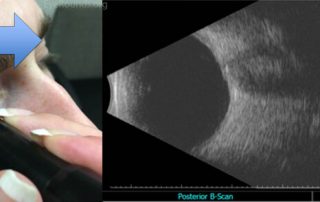

برای تشخیص برخی از بیماری های چشم که نیازمند اطلاعاتی از کره چشم و فضای پشت چشم می‌باشد، سونوگرافی چشم توصیه می‌شود. سونوگرافی چشم به دو دسته سونوگرافی از روی پلک و سونوگرافی از سطح قرنیه تقسیم می‌شود. با سونوگرافی چشم می‌توان وجود تومورهای چشمی را نیز بررسی کرد. نکاتی که قبل از سونوگرافی چشم [...]